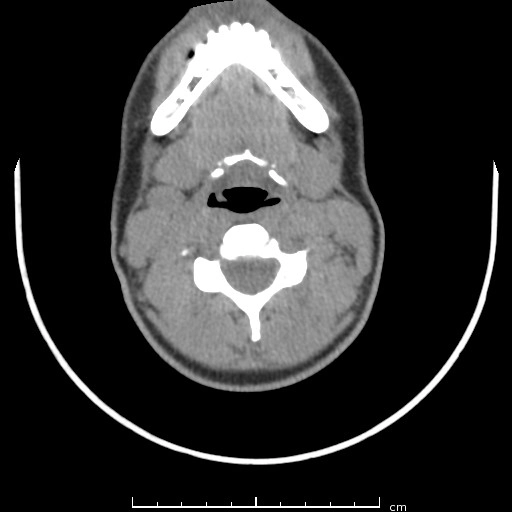

Nang khe mang (Branchial cleft cyst)